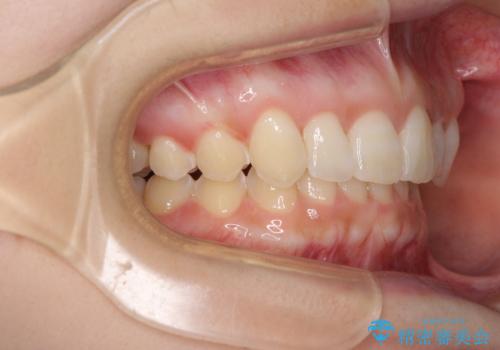

- 前歯のデコボコ気になるとのことで来院された患者様です。

下顎骨が上顎骨に対して右側にシフトしており、さらに下顎が後方に位置しているため、非常に強い咬合力で食いしばっている状態でした。

上下顎ともに歯列全体の後方移動とIPR(歯と歯の間を削る)によってデコボコが解消するように設計し、インビザラインにより治療を行うこととしました。

強い咬合力による臼歯部の噛みにくさと、それに伴う歯の移動の鈍さに悩まされ、非常に長い期間を要することとなりました。

上下正中位置は、治療開始時よりは改善したものの、ここが限界であろうというところでのゴールとなりました。

下顎前歯の大半が隠れている状態ですが、左右への歯ぎしりはスムーズに行うことができ、就寝時には後戻り防止も兼ねて、食いしばり対策としてマウスピースの使用を継続するようお願いしております。